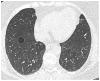

Objective: To investigate the prevalence and natural course of pulmonary cysts in a population-based cohort and to describe the CT image characteristics in association with participant demographics and pulmonary functions.

Materials and methods: Chest CT scans of 2633 participants (mean age 59.2 years; 50% female) of the Framingham Heart Study (FHS) were visually evaluated for the presence of pulmonary cysts and their image characteristics. These findings were correlated with participant demographics and results of pulmonary function tests as well as the presence of emphysema independently detected on CT. The interval change was investigated by comparison with previous CT scans (median interval 6.1 years).

Results: Pulmonary cysts were seen in 7.6% (95% CI 6.6% to 8.7%; 200/2633). They were not observed in participants younger than 40 years old, and the prevalence increased with age. Multiple cysts (at least five) were seen in 0.9% of all participants. Participants with pulmonary cysts showed significantly lower body mass index (BMI) (p<0.001). Pulmonary cysts were most likely to appear solitary in the peripheral area of the lower lobes and remain unchanged or slightly increase in size over time. Pulmonary cysts showed no significant influence on pulmonary functions (p=0.07-0.6) except for diffusing capacity of the lung for carbon monoxide (DLCO) (p=0.03) and no association with cigarette smoking (p=0.1-0.9) or emphysema (p=0.7).

Conclusions: Pulmonary cysts identified on chest CT may be a part of the aging changes of the lungs, occurring in asymptomatic individuals older than 40 years, and are associated with decreased BMI and DLCO. Multiple pulmonary cysts may need to be evaluated for the possibility of cystic lung diseases.